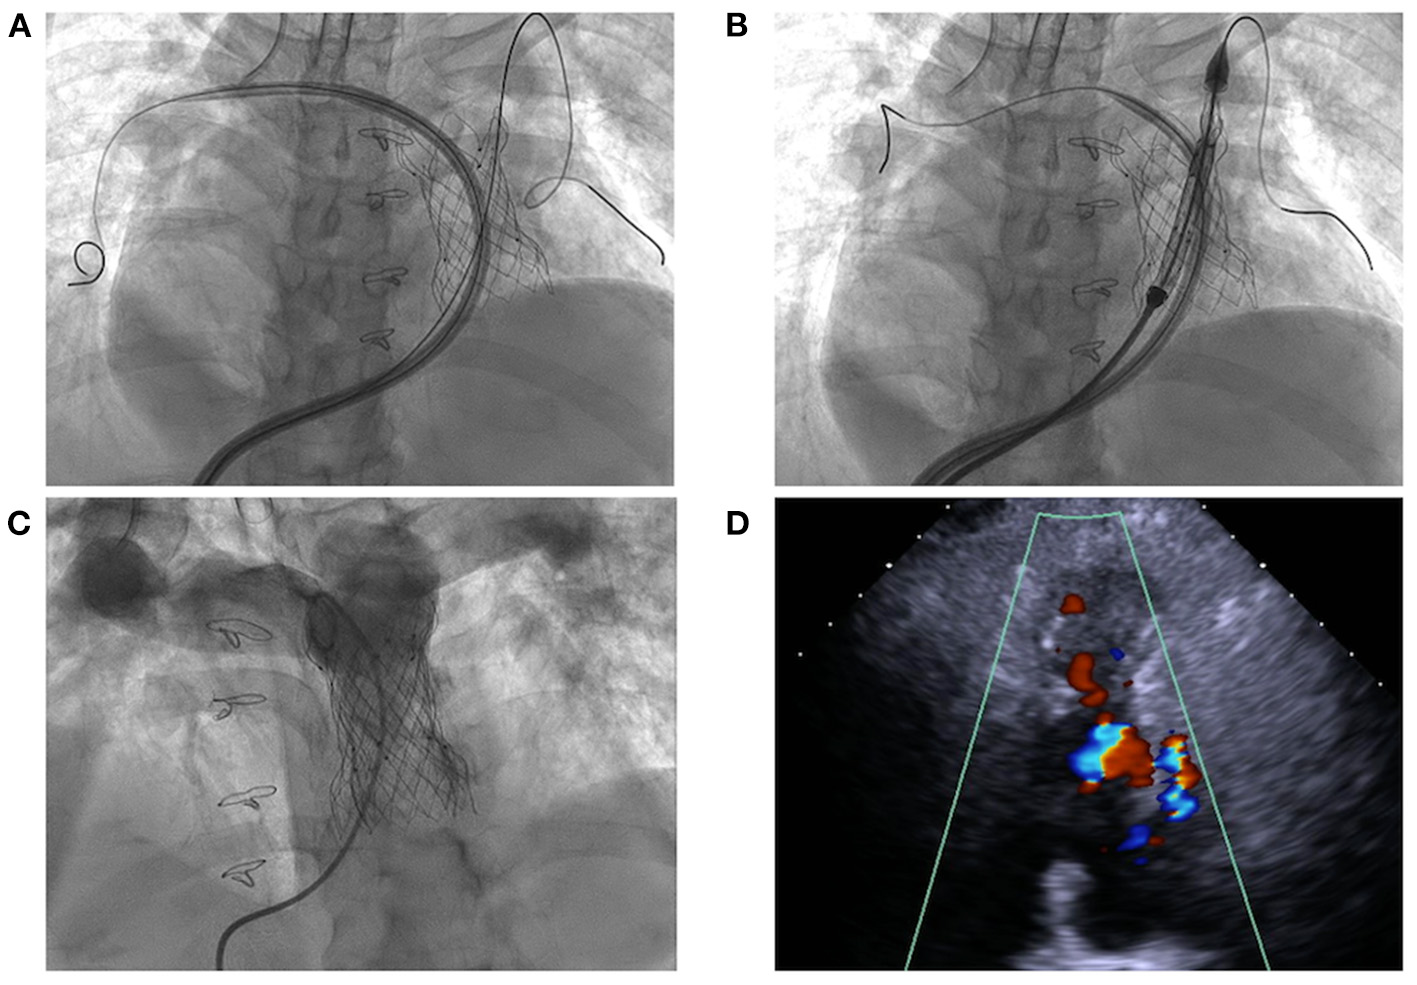

The procedure was performed with fluoroscopic and TTE guidance under general anesthesia. Bilateral femoral veins were used, and right heart catheterization was first executed. Pulmonary artery pressure was 35/8 mmHg and right ventricle pressure was 50/8 mmHg. Severe pulmonary insufficiency appeared on angiography (Figure 1B; Supplementary Video 2). After pre-dilation with a 25 mm × 50 mm (diameter × length) balloon (Balt, Montmorency, France), systolic pressure gradient across the bioprosthesis decreased from 15 mmHg to 6 mmHg. Since the annular size of 25.9 mm calculated on computed tomography and three-dimension reconstruction (Figure 1C), a P28-25 mm (diameter-length) self-expandable Venus P-valve (Venus Medtech, Hangzhou, China) with 22-F delivery system was planned to be deployed. The process was beset with difficulties in advancing the delivery sheath. The buddy wire technique, which was employed with two Lunderquist wires, was attempted but the delivery system still failed to be advanced and positioned appropriately. Finally, the 14-F Cook sheath (Cook Medical, Bloomington, USA) was advanced over the second Lunderquist wire, which passed through the RVOT and placed in the distal of right pulmonary artery. The 14-F Cook sheath served as modified buddy wire providing extra support and straightening the vessel and the RVOT (Figure 2A). Maneuvering the 22-F Venus P delivery system alongside the 14-F Cook sheath aided in the advancement of the delivery system into the proximal end of left pulmonary. Prior to the deployment of the second pulmonary valve, the 14-F Cook sheath was pulled back into inferior vena cava. The new self-expanding valve was then successfully delivered (Figure 2B) and implanted. Post-dilation with a 25 mm × 50 mm (diameter × length) balloon (Balt, Montmorency, France) was performed to better shape for the stent strut and RVOT. Post-procedure angiography and TTE showed no pulmonary regurgitation (Figures 2C,D, 3; Supplementary Videos 3, 4). Then pulmonary pressure was raised to 35/18 mmHg.

Figure 2

Transcatheter pulmonary valve-in-valve implantation for degenerated bioprosthesis. (A,B) The delivery system crossed the degenerated bioprostheses with the assistance of modified buddy wire; (C,D) The result of transcatheter valve-in-valve implantation with no pulmonary regurgitation.